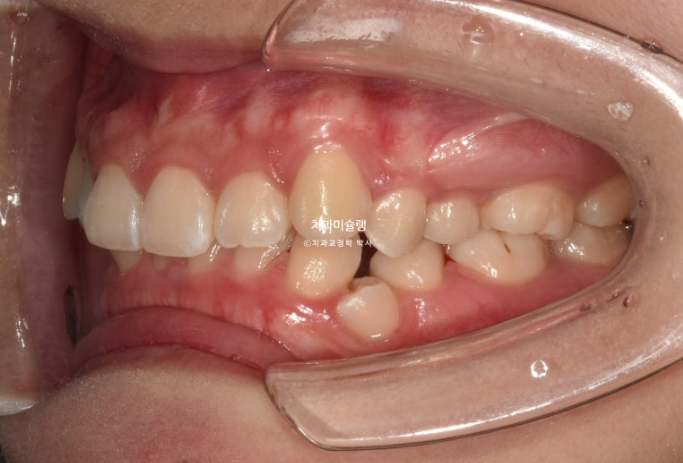

중심선이 약 2mm 어긋나 있으며 송곳니 덧니가 보입니다.

위 아래 앞니가 깊게 물리는 과개교합도 보입니다.

웃을때 잇몸이 많이 보이는 거미스마일이 있습니다. 특히 위 앞니가 뒤로 쓰러진 옥니 입니다.

작은어금니 하나가 매복되었다시피 깊게 누워있습니다.

치료계획은 누워있는 덧니를 포함해서 작은어금니 4개 발치

단 입이 너무 들어가는 것은 원치 않아 모르페우스 시뮬레이션을 통해 앞니 들어가는 양을 2mm정도로 제한하기로 합니다.